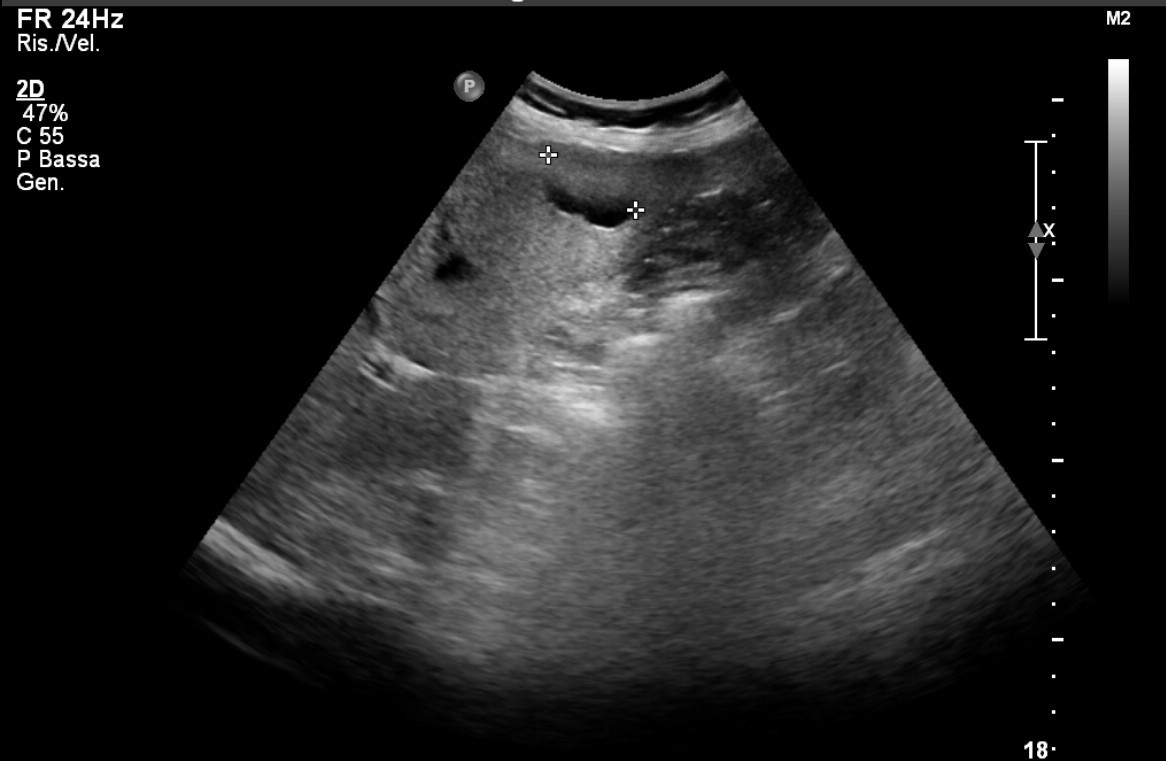

Ad oggi sono state identificate con l’ecografia addominale prevista dal protocollo, 9 neoplasie del parenchima epatico: 5 angiosarcomi (Fig. 1-4) (di cui 2 viventi) e 4 epatocarcinomi (Fig. 5-7) (di cui 1 vivente), successivamente sottoposte a studio TC e tutte confermate dalla diagnosi istologica.

I dati confermano la correlazione tra esposizione occupazionale al CVM e sviluppo di angiosarcoma epatico e carcinoma epatocellulare, come riportato in letteratura. Inoltre, l’ecografia prevista nel programma di Sorveglianza Sanitaria adottato, ha consentito l’identificazione precoce di neoplasie epatiche, assumendo un ruolo fondamentale nel follow-up di questi pazienti e permettendo un tempestivo approccio clinico-terapeutico.

Tuttavia, l’indagine ecografica non permette di effettuare la diagnosi differenziale tra HCC e angiosarcoma epatico: per la diagnosi di certezza è necessaria la conferma istologica.

Fig.5. Caso di HCC

Fig.6. Caso di HCC